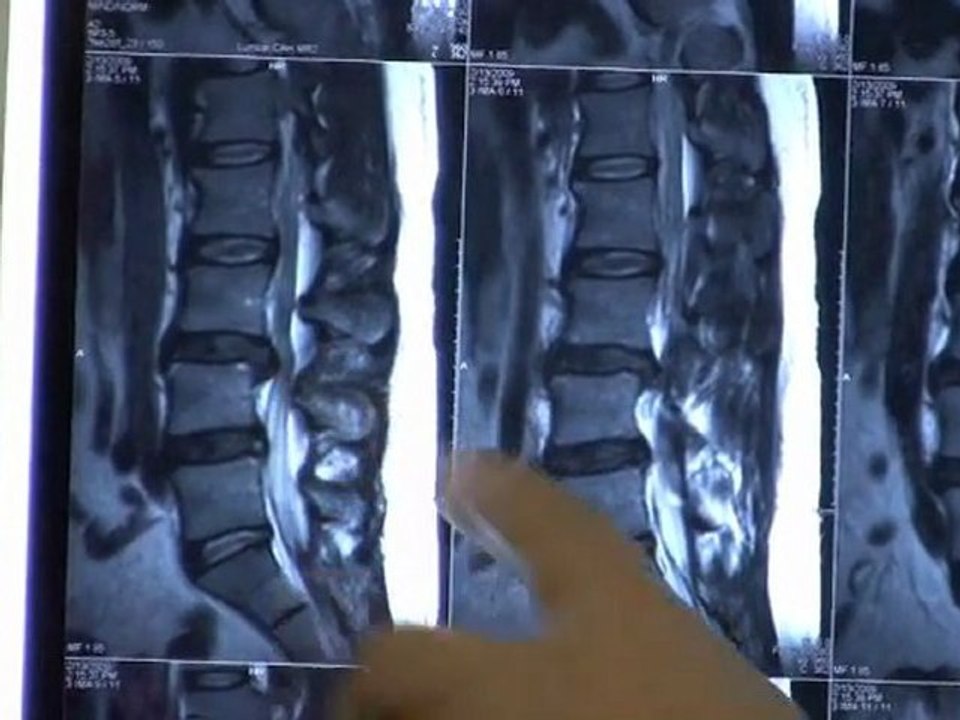

http://www.triangledisc.com. - Eva suffered with sciatic leg pain for months as a result of a bulging disc. She "absolutely" recommends Spinal Decompression Therapy at Triangle Disc Care. <br /><br />Triangle Disc Care <br />2413 Blue Ridge Rd <br />Raleigh, NC 27607 <br />(919) 571-2515 <br /><br />http://www.triangledisc.com/decompression.php <br />http://www.triangledisc.com/backpain.php <br />http://youtu.be/_hkZxqUnjgg